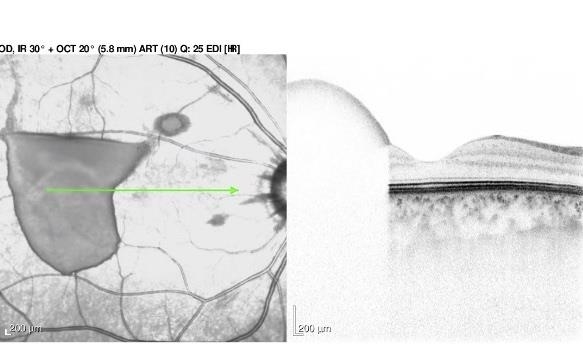

- OCT of retrohyaloid hemorrhage.